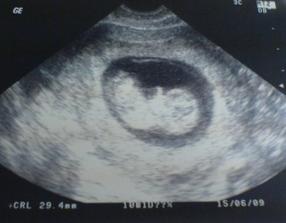

18.září jsme byli na našem 1.IVF... a 8.den od ET se mi "zjevily" nádherné // 🙂... přeju si,aby se všechno vyvíjelo dobře... 29.9 11.den po ET mi pro zhoršení OHSS provedli punkci Douglasova prostoru a odsáli 2 litry žlutého ascitu ☹ Nicméně se mi ulevilo 🙂 HCG ten den 259... 6.10 kontrola HCG - 2950 (18.den od ET)... 10.10 UTZ - čekáme DVOJČÁTKA 🙂 🙂 🙂... 17.10 krvácení a následná hospitalizace, UTZ - dvojčátkům bijí srdíčka, 20.10 HCG - 56000, 25.10 propuštění z nemocnice... 31.10 poslední kontrola v CARu, dvojčátka mají 2 a 2,1 cm... 11.11 UTZ - dvojčátka mají 3 cm... 24.11 UTZ - dvojčátka mají 9 cm (ale moc se mi to měření nezdá, ve čtvrtek na screeningu se ukáže pravda, čeká nás 3D 🙂) 27.11 screening I.trimestru - miminka jsou zdravá, od hlavičky po prdelku mají 7 cm... 19.12 3D - miminko "A" je chlapeček, "béčko" chce zůstat zatím v utajení 🙂 tak snad příště 🙂... 8.1 3D - miminko "B" je holčička 🙂 19.1 echokardiografie - obě srdíčka jsou zdravá 🙂 20.1 screening II.trimestru - vše OK, miminka mají 360 a 364 gramů 🙂 26.1 UTZ - chlapečkovi se ztratil pindík a najednou čekáme 2 holčičky 🙂) Doufám, že už je to definitivní 🙂) 19.2 UTZ 3D4 - holčičky potvrzeny!!! 🙂 mají každá téměř 800 gramů! 🙂 20.3 UTZ - holčičky mají 1700 a 1800 gramů! 8.4 UTZ - holky mají neuvěřitelné váhy 2415 a 2600 gramů! 11.5 nástup do nemocnice... 11.května ve 20,03 se nám akutním císařským řezem narodila Eliška (2970/48) a o minutu později Nelinka (3200/50).Jsme nejšťastnější rodiče na světě! 🙂